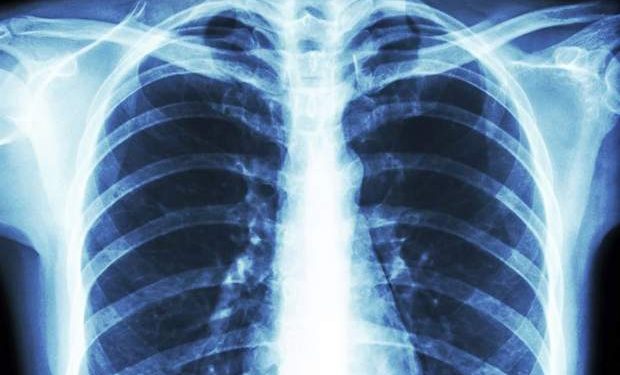

ریاحی در خصوص التهاب ریه در بیماران کرونایی یادآور شد: ذاتالریه یا التهاب ریه همیشه تاریخ تهدیدی برای سلامت انسان بوده و کرونا هم یکی از علل التهاب ریه است، در التهاب ریه هم طیفی داریم از درگیری خفیف تا شدید، درگیری ریه در درصد کم و ناچیزی از بیماران کرونایی شکل میگیرد، اما اغلب مردم فکر میکنند چون کرونا گرفتند حتما ریه آنها درگیر است، ما درگیری ریه را در همه بیماران نداریم خیلی از بیماران هیچ علامتی ندارند، فرد در تماس بوده از سر کنجکاوی میرود یک تست میدهد میبیند که کرونا دارد اما اصلا هیچ علامتی ندارد و این طور نیست که چون علامت ندارد ریه از داخل در حال از بین رفتن است.

این فوق تخصص ریه با اشاره به اینکه مشکل اینجاست که خیلی از افراد خودشان کنجکاو هستند و اصرار به گرفتن عکس دارند، اظهار کرد: به همین دلیل در بخشهای سی تی اسکن صف میکشند، حالا یک لکهای هم در ریهشان پیدا میکنند و میگویند پنج یا ۱۰ درصد ریه درگیر شده، افرادی که در عکس ریهشان این درگیری دیده میشود حتی اگر هم بستری شوند بعد از بهبودی این التهاب برطرف خواهد شد و حالشان کاملا خوب میشود، ممکن است بعد از بهبودی نیز باز هم این لکه در عکس دیده شود چون معمولا برای از بین رفتن این لکه در عکس چند هفته تا دو ماه زمان لازم است.

رئیس بیمارستان رسول اکرم(ص) در پایان در خصوص دلائل پائین آمدن سطح اکسیژن در ریه و خون نیز عنوان کرد: ریه شبیه درختی است که از سمت ساقه به داخل آن میروید، یعنی نای تنه درخت است و سمت راست و چپ شاخههای آن هستند که منشعب شدهاند، داخل این مسیر فقط هوا جریان دارد تا جایی که در سطح بافت ریه بتواند در نزدیکترین مجاورت با خون تبادل اکسیژن و دیاکسیدکربن کند، اتفاقی که درکرونا میافتد این است که ریه سنگین شده و نسج از بین میرود و بافت احتقان پیدا میکند، شلوغی بافت باعث میشود که نتواند کار طبیعی خود را انجام دهد و بعد میشنویم که سطح اکسیژن در خون یا ریه بیمار افت کرده که این اتفاق به دلیل التهاب بافت ریه است./برنا